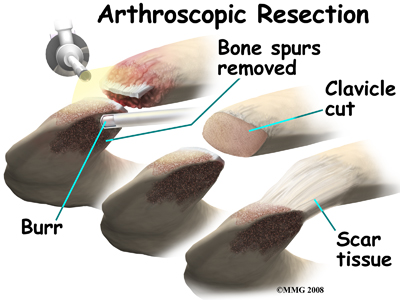

If nonsurgical measures fail to relieve your pain, your doctor may recommend surgery.

The most common procedure for AC joint osteoarthritis is resection arthroplasty. A resection arthroplasty involves removing a small portion of the end of the clavicle. This leaves a space between the acromion (the piece of the scapula that meets your shoulder) and the cut end of the clavicle, where the joint used to be. Your surgeon will take care not to remove too much of the end of the clavicle to prevent any damage to the ligaments holding the joint together. Usually only a small portion is removed, less than one cm (about three-eighths of an inch). As your body heals, the joint is replaced by scar tissue. Remember, the AC joint doesn't move much, but it does need to be flexible. The scar tissue allows movement but stops the bone ends from rubbing together.

This procedure can be done in two ways. Today, it is more common to do this procedure using the arthroscope. An arthroscope is a slender tool with a tiny TV camera on the end. It lets the surgeon work in the joint through a very small incision. This may result in less damage to the normal tissues surrounding the joint, leading to faster healing and recovery.

The older open method of performing this operation is done by making a small incision, less than two inches long, over the AC joint. The AC joint is very close to the surface of the skin and can be easily reached through a small incision. The surgeon can then use a special saw or other instrument to shave off a small portion of the end of the clavicle.